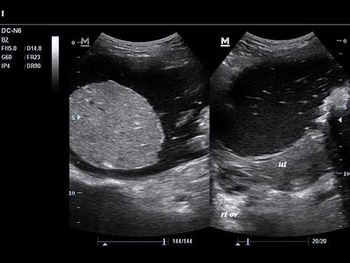

Challenge your diagnostic skills: What's causing this woman's pelvic discomfort?

Challenge your diagnostic skills with these images of a pelvic mass.